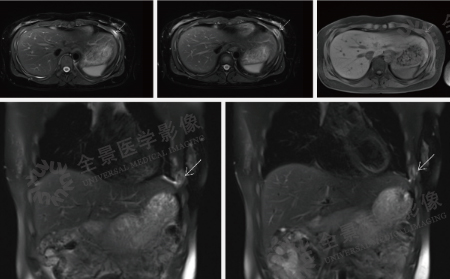

案例:中年女性,纳差,腹胀3周,否认乙肝病史,外院CT示:肝内低密度灶,腹盆腔大量积液。左肾囊肿。肝脏轮廓光整,肝左右叶比例正常,肝左叶外侧段见类楠圆形囊状水样信号灶,长径约20mm,增强扫描未见强化。肝内未见异常强化灶。肝内血管走行正常,肝内、外胆管未见扩张。下腔静脉肝段呈扁线状改变。胆囊大小正常,壁未见增厚,囊内未见异常信号。脾脏增大,信号未见异常,增强未见异常强化。胰腺形态、大小正常,信号均匀,增强未见异常强化,胰管未见扩张。双侧肾脏大小、位置、形态正常,双肾实质内见数枚囊状水样信号灶,大者位于左肾,长径约21mm。双侧肾上腺形态及信号未见异常。全腹大量腹水,包括网膜囊下隐窝大量腹水,腹膜后未见肿大的淋巴结。

结论:1.布加综合征;2.肝左叶外侧段囊肿;3.双肾囊肿。